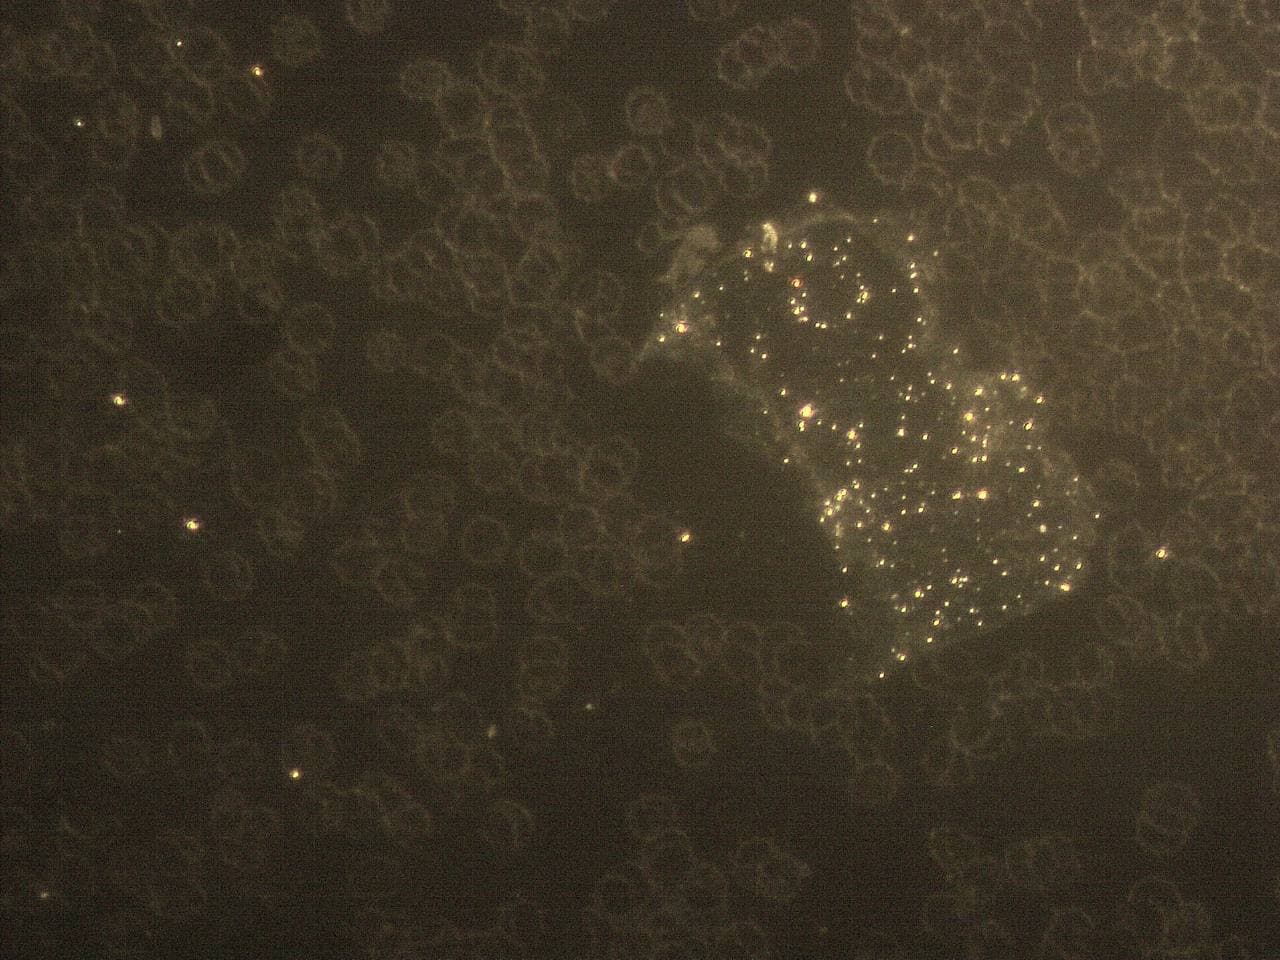

GENimpfschaden

im Blutbild einer GENgeimpften Person

15.9.2021: 9 Fotos

Impfschäden Schweiz

Coronaimpfung, [15.09.21 13:19]

https://t.me/Impfschaden_Corona_Schweiz/21521

[Weitergeleitet aus Holger Fischer

Rechtsanwalt (Maya Stella)]

Im folgenden wieder Blutbilder von Blut von

Geimpften, mit Verunreinigungen

(Dunkelfeldmikroskopie) |

GENimpfschaden

im Blutbild 15.9.2021: Foto 1

Impfschäden Schweiz Coronaimpfung, [15.09.21

13:19]

https://t.me/Impfschaden_Corona_Schweiz/21522

[Weitergeleitet aus Holger Fischer Rechtsanwalt

(Maya Stella)]

Scheibenartiges Gebilde mit leuchtenden Punkten

GENimpfschadne im Blutbild 15.9.2021: Foto 1

[37] |

GENimpfschaden

im Blutbild 15.9.2021: Foto 2

Impfschäden Schweiz Coronaimpfung, [15.09.21

13:19]

https://t.me/Impfschaden_Corona_Schweiz/21523

[Weitergeleitet aus Holger Fischer Rechtsanwalt

(Maya Stella)]

Scheibenartige Form mit Spike Proteinen (?)

GENimpfschaden im Blutbild 15.9.2021: Foto 2

[38]